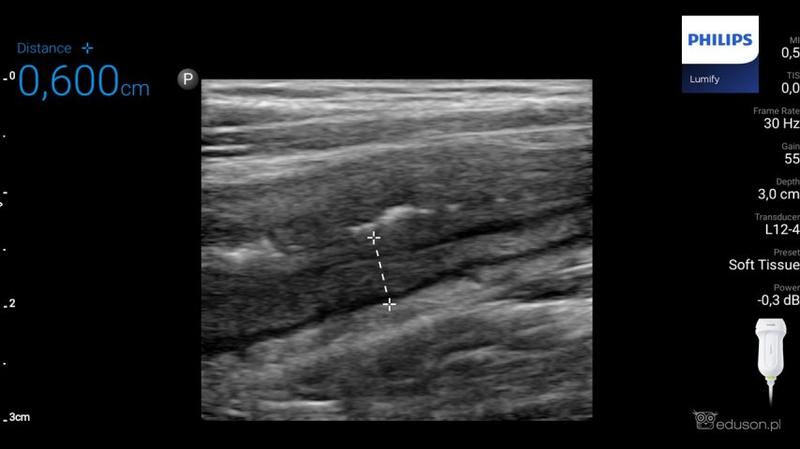

Ultrasonografia, znana w skrócie jako USG, stanowi jedno z badań, które od razu przychodzi na myśl, gdy rozważamy diagnostykę medyczną. Warto jednak zauważyć, że kiedy mówimy o wykrywaniu nowotworów, szczególnie raka jelita grubego, USG nie pokazuje pełni swoich możliwości. Ma swoje ograniczenia, zwłaszcza w przypadku małych zmian, a diagnostyka wczesnych stadiów nowotworów nie zagwarantuje najlepszych wyników. Możemy porównać USG do dobrego kucharza, który przyrządza znakomity obiad, ale zapomniał o soli – wszyscy odczuwają, że czegoś brakuje, ale nikt nie potrafi dokładnie zidentyfikować problemu.

W dodatku obrazowanie ultrasonograficzne charakteryzuje się szczególnymi cechami. Z łatwością wykrywa duże guzy, które mogłyby nawet zabierać głos w karaoke, natomiast rozpoznawanie subtelnych, małych zmian, które mogą w przyszłości przekształcić się w nowotwory, sprawia jej trudności. Dlatego poleganie wyłącznie na USG w kontekście wykrywania raka jelita grubego przypomina kupowanie losu na loterii – lepiej mieć różne metody w zasięgu ręki, aby zwiększyć swoje szanse na sukces. Warto więc rozważyć takie alternatywy, jak kolonoskopy, tomografy komputerowe czy rezonanse magnetyczne, które dostarczają znacznie więcej informacji niż wywiad w programie plotkarskim.

| Ultrasonografia (USG) | Badanie obrazowe wykrywające duże guzy w jelicie grubym. | Nieefektywna w wykrywaniu małych zmian i wczesnych stadiów nowotworów. |

Ultrasonografia (USG) nie jest wystarczająco efektywna w wykrywaniu małych zmian i wczesnych stadiów nowotworów, co czyni ją mniej przydatną w kontekście raka jelita grubego. Dobrze radzi sobie tylko z dużymi guzami, co ogranicza jej przydatność jako pierwszego wyboru w diagnostyce.